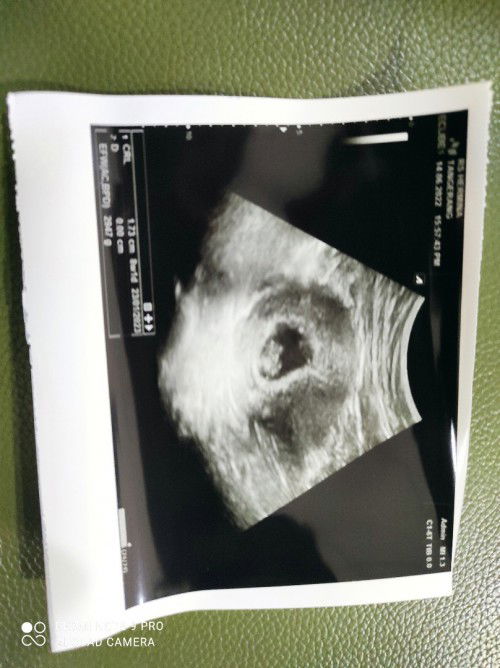

Ada yang sama kah? USG transvaginal 7W5D sdh ada janin dan detak jantung normal. Setelah itu dikasih resep microgest 200mg , besok nya malah nge flek sdh 3hr ini bedrest masih nge flek darah merah muda. Saya sdh konsultasi ke dokter kandungan yg kemarin USG dan bidan dekat rumah, malah dianjurkan tambah dosis microgest menjadi 2x1. Saya khawatir bgt malah takut kenapa-napa kehamilan pertama penantian 10th. #seriusnanya #bantusharing #ingintahu #pleasehelp #firstbaby #firstmom

Bun, saya mau tanya. Tgl 4 April saya USG kehamilan 7W5D sdh ada janin dan detak jantungnya. Dikasih dokter obat penguat kandungan dan obat pengencer darah. Besoknya malah keluar flek darah dan nyeri perut. Hari ini konsultasi ke bidan, bidan bilang kecapean harus bedrest total 5hr. Tunggu sampe tgl 15 USG lagi. Ada yg sama kah bund? Kehamilan trimester 1 nge flek? Bahaya kah? Pdhl aku hamil gak merasakan lemas, mual, makan apa saja masuk. Tapi kenapa bisa nge flek 🥺🥺#seriusnanya #bantusharing #ingintahu #pleasehelp #firstbaby #firstmom